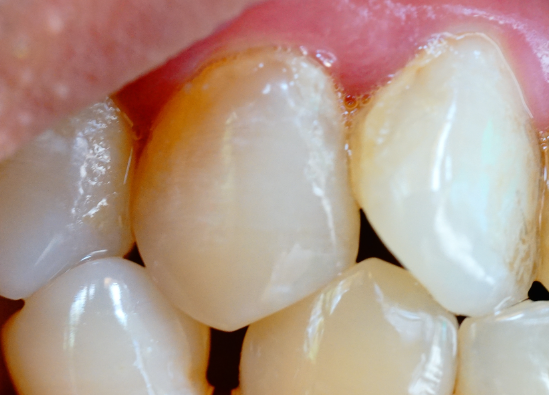

承德人補(bǔ)牙前注意了!很多人花了錢、遭了罪補(bǔ)牙,結(jié)果沒幾天就出現(xiàn)材料脫落、繼發(fā)齲等問題,甚至需要重新補(bǔ)牙,相當(dāng)于白做了!其實(shí),補(bǔ)牙的效果不僅取決于醫(yī)生技術(shù)和材料質(zhì)量,還和補(bǔ)牙前的準(zhǔn)備工作息息相關(guān)。今天惟…